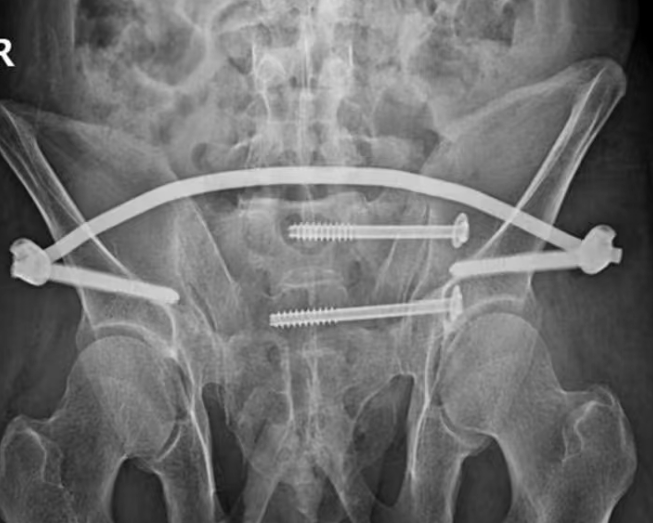

患者入院后,完善相关检查,诊断为:1.骨盆骨折(前后环损伤)2.右侧第1后肋、8-10前肋骨折 3.腰2左侧横突骨折。

李东柱副主任医师带领付开封,郭强医师立即制定详细手术方案,在麻醉科配合下,应用骨科机器人行骨盆后环第1、2骶髂关节螺钉固定+前环Infix内固定,手术顺利,术后护理团队精心照护,手术成功,尽最大努力实现了骨盆完美复位及精准螺钉置入、固定。

术后患者复查拍片骨折复位及固定良好,患者自我感觉良好,疼痛大大缓解,在床上可以随意翻身及坐起活动,约术后6-8周即可下地活动。术后给予进行指导康复,患者进行积极功能康复,待骨折愈合以后,肯定会有一个良好的功能。